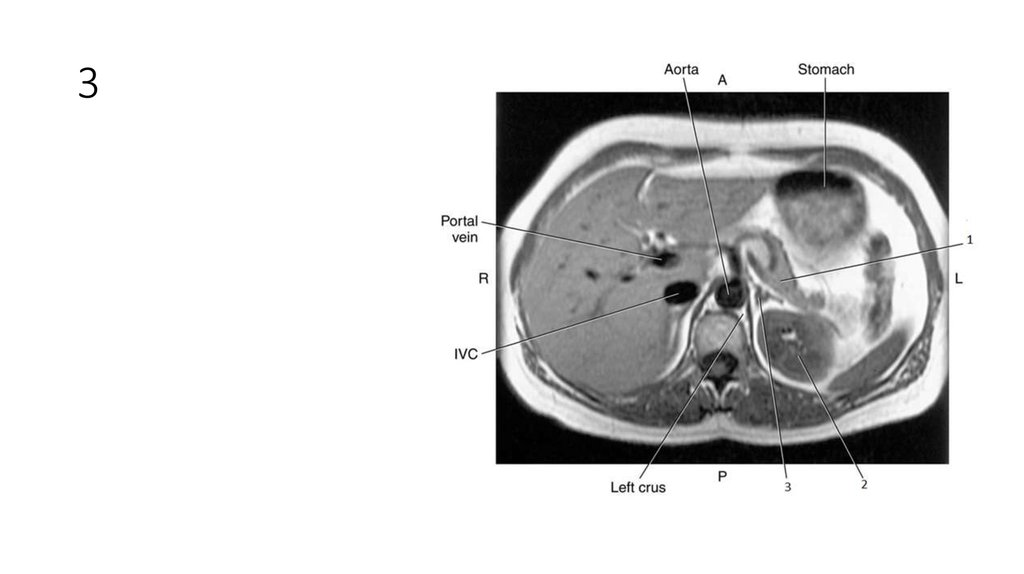

16. 1

17. 1

• Falciform Ligament

18. 2

19. 2

• Left lobe of Liver

20. 3

21. 3

• Spleen

22. 4

23. 4

• Aorta